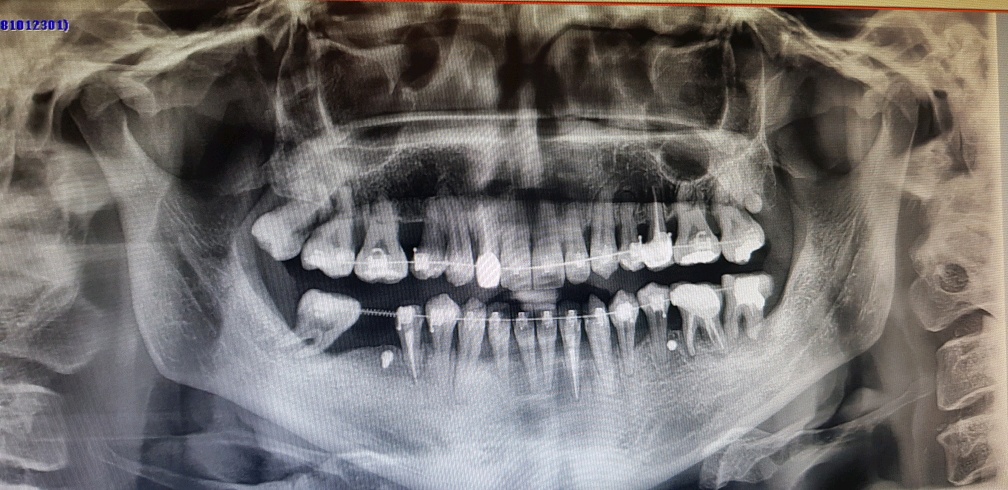

이게 몇일 전 찍었던 엑스레이 사진인데

그래도 처음보다 상당히 낳아진 치아 상태죠;;

오른쪽 윗쪽 어금니 부분 보면 사랑니가 튀어나와있는게 보일겁니다.

이게 확대한 부분인데 좌측에 보이는건 필요없는 사랑니라서 음식물도 끼고 하기에

제거하는게 좋다고 하더군요;;